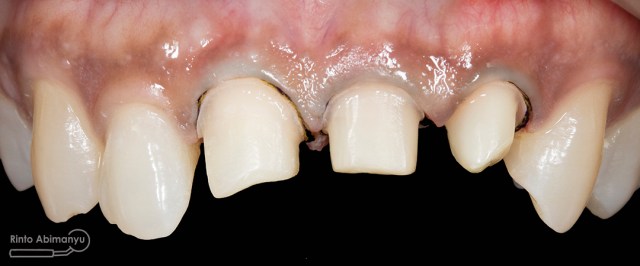

ini hasil preparasi gigi-giginya…

Hasil preparasi tampak depan

Hasil preparasi tampak oklusal